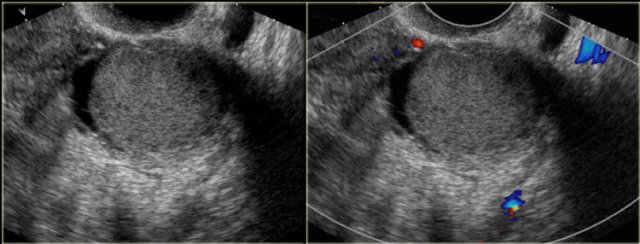

The transvaginal ultrasound images show a small complex ovarian cyst with wall vascularity on power Doppler analysis.

The characteristic circular Doppler appearance is called the 'ring of fire'.

Note, there is good through-transmission and no internal vascularity, consistent with a, partially involuted, corpus luteum cyst.

Corpus luteum cyst Corpus luteum cyst

Another case with the typical the 'ring of fire' on ultrasound.

Corpus luteum cyst at MRI: an axial T2-weighted image demonstrating an involuting corpus luteum cyst (arrow).

This is a normal finding.

The right ovary is also normal.